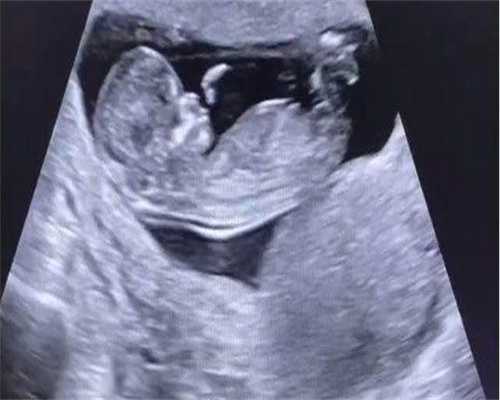

试管婴儿与剖腹产试管婴儿是指通过辅助生殖技术,将受精卵在体外培养后再植入自己体内子宫内发育。对于试管婴儿而言,并不一定需要进行剖腹产。根据孕周、胎位和母婴状况等因素,医生会评估最适合的分娩方式。

虽然试管婴儿在胚胎移植后可能存在一些风险(如胎盘功能障碍),但大部分情况下仍可以顺利经历自然分娩过程。当然在某些特殊情况下(如多胞胎、羊水过少或高龄等),医生可能会建议进行剖腹产以确保母婴的安全。